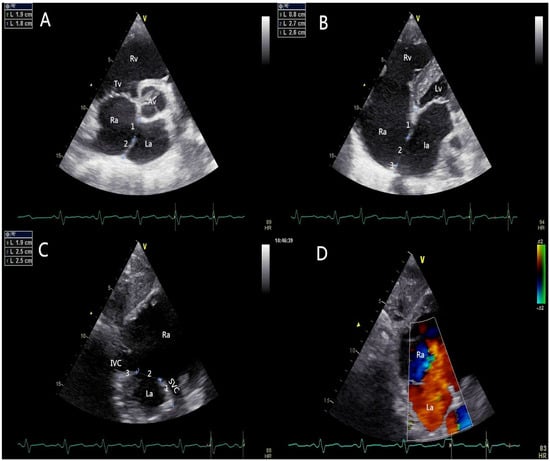

All patients should be evaluated using TTE in terms of defect size, location, rims, adjacent structures, and cardiac function. The edge of the defect was divided into six areas according to their locations or neighboring structures (Figure 2): upper rim (Up-r), atrioventricular valve rim (AVV-r), aortic rim (Ao-r), posterior rim (Po-r), SVC rim (SVC-r), and IVC rim (IVC-r). A floppy septum was considered a normal rim. A “Union Score” was utilized to select patients who were suitable for PAC (Table 1).

Figure 2.

Pre-procedural transthoracic echocardiographic assessment. (A) The short-axis left parasternal view of aortic valve delineated the aortic rim and the posterior rim of the defect; (B) The four-chamber view showed the atrioventricular valve rim and the upper rim; (C) The short axis subcostal view showed the SVC rim and IVC rim; (D) The short axis subcostal view (coloured) showed the blood flow cross the atrial septum (left to right). AV: aortic valve; RA: right atrium; LA: left atrium; RV: right ventricle; LV: left ventricle; TV: tricuspid valve; IVC: inferior vena cava; SVC: superior vena cava.

The figure shows the transthoracic echocardiographic view of ASD without an aortic rim in a 73-year-old patient (Union Score = 0 + 3 + 3 + 2 + 3 + 3 = 14 points). The short-axis left parasternal view of the AV delineated the entire length of the ASD (3A-1), the aortic rim (deficient, 0 points), and the posterior rim (3A-2, 19 mm, 3 points). The four-chamber view shows the atrioventricular valve rim (3B-3, 26 mm, 3 points) and the upper rim (3B-1, 8 mm, 2 points), and the maximum length of the ASD (3B-2) could be observed in this view. The short-axis subcostal view shows the length of the defect (3C-2), the SVC rim (19 mm, 3 points), and the IVC rim (25 mm, 3 points). The figure shows the transthoracic echocardiographic view of the ASD with an adequate SVC rim and an adequate IVC rim. The short-axis subcostal view (colored) shows the blood flow across the atrial septum (left to right) (3D).